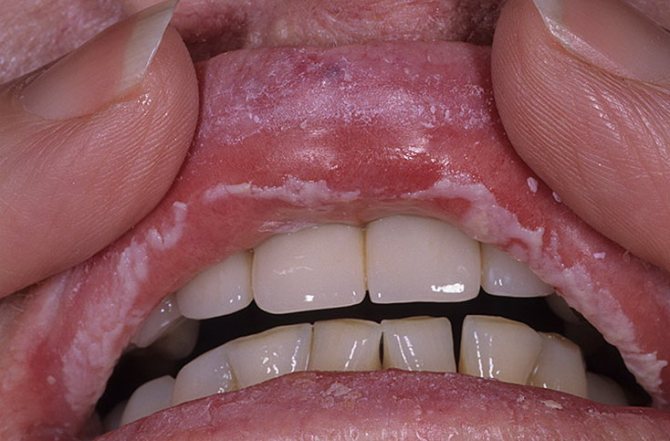

- Лейкоплакия. Заболевание такого рода предполагает появление ороговевших участков на слизистой оболочке десен в виде твердых белых или серых бляшек. Подобная патология может быть связана с механическими или термическими повреждениями тканей (неправильно поставленная пломба, чрезмерно горячая пища и т. д.) или табакокурением.

- Белые шелушащиеся области – плоский лишай. Причины: аллергия по фоне гепатита С, использование жевательного табака. Усугубление состояния развивается злоупотреблением курения, приема алкоголя, что при плоском лишае может привести к развитию рака. При этом пятна распространяются на десны (про кровоточивость десен смотрите тут) и горло.